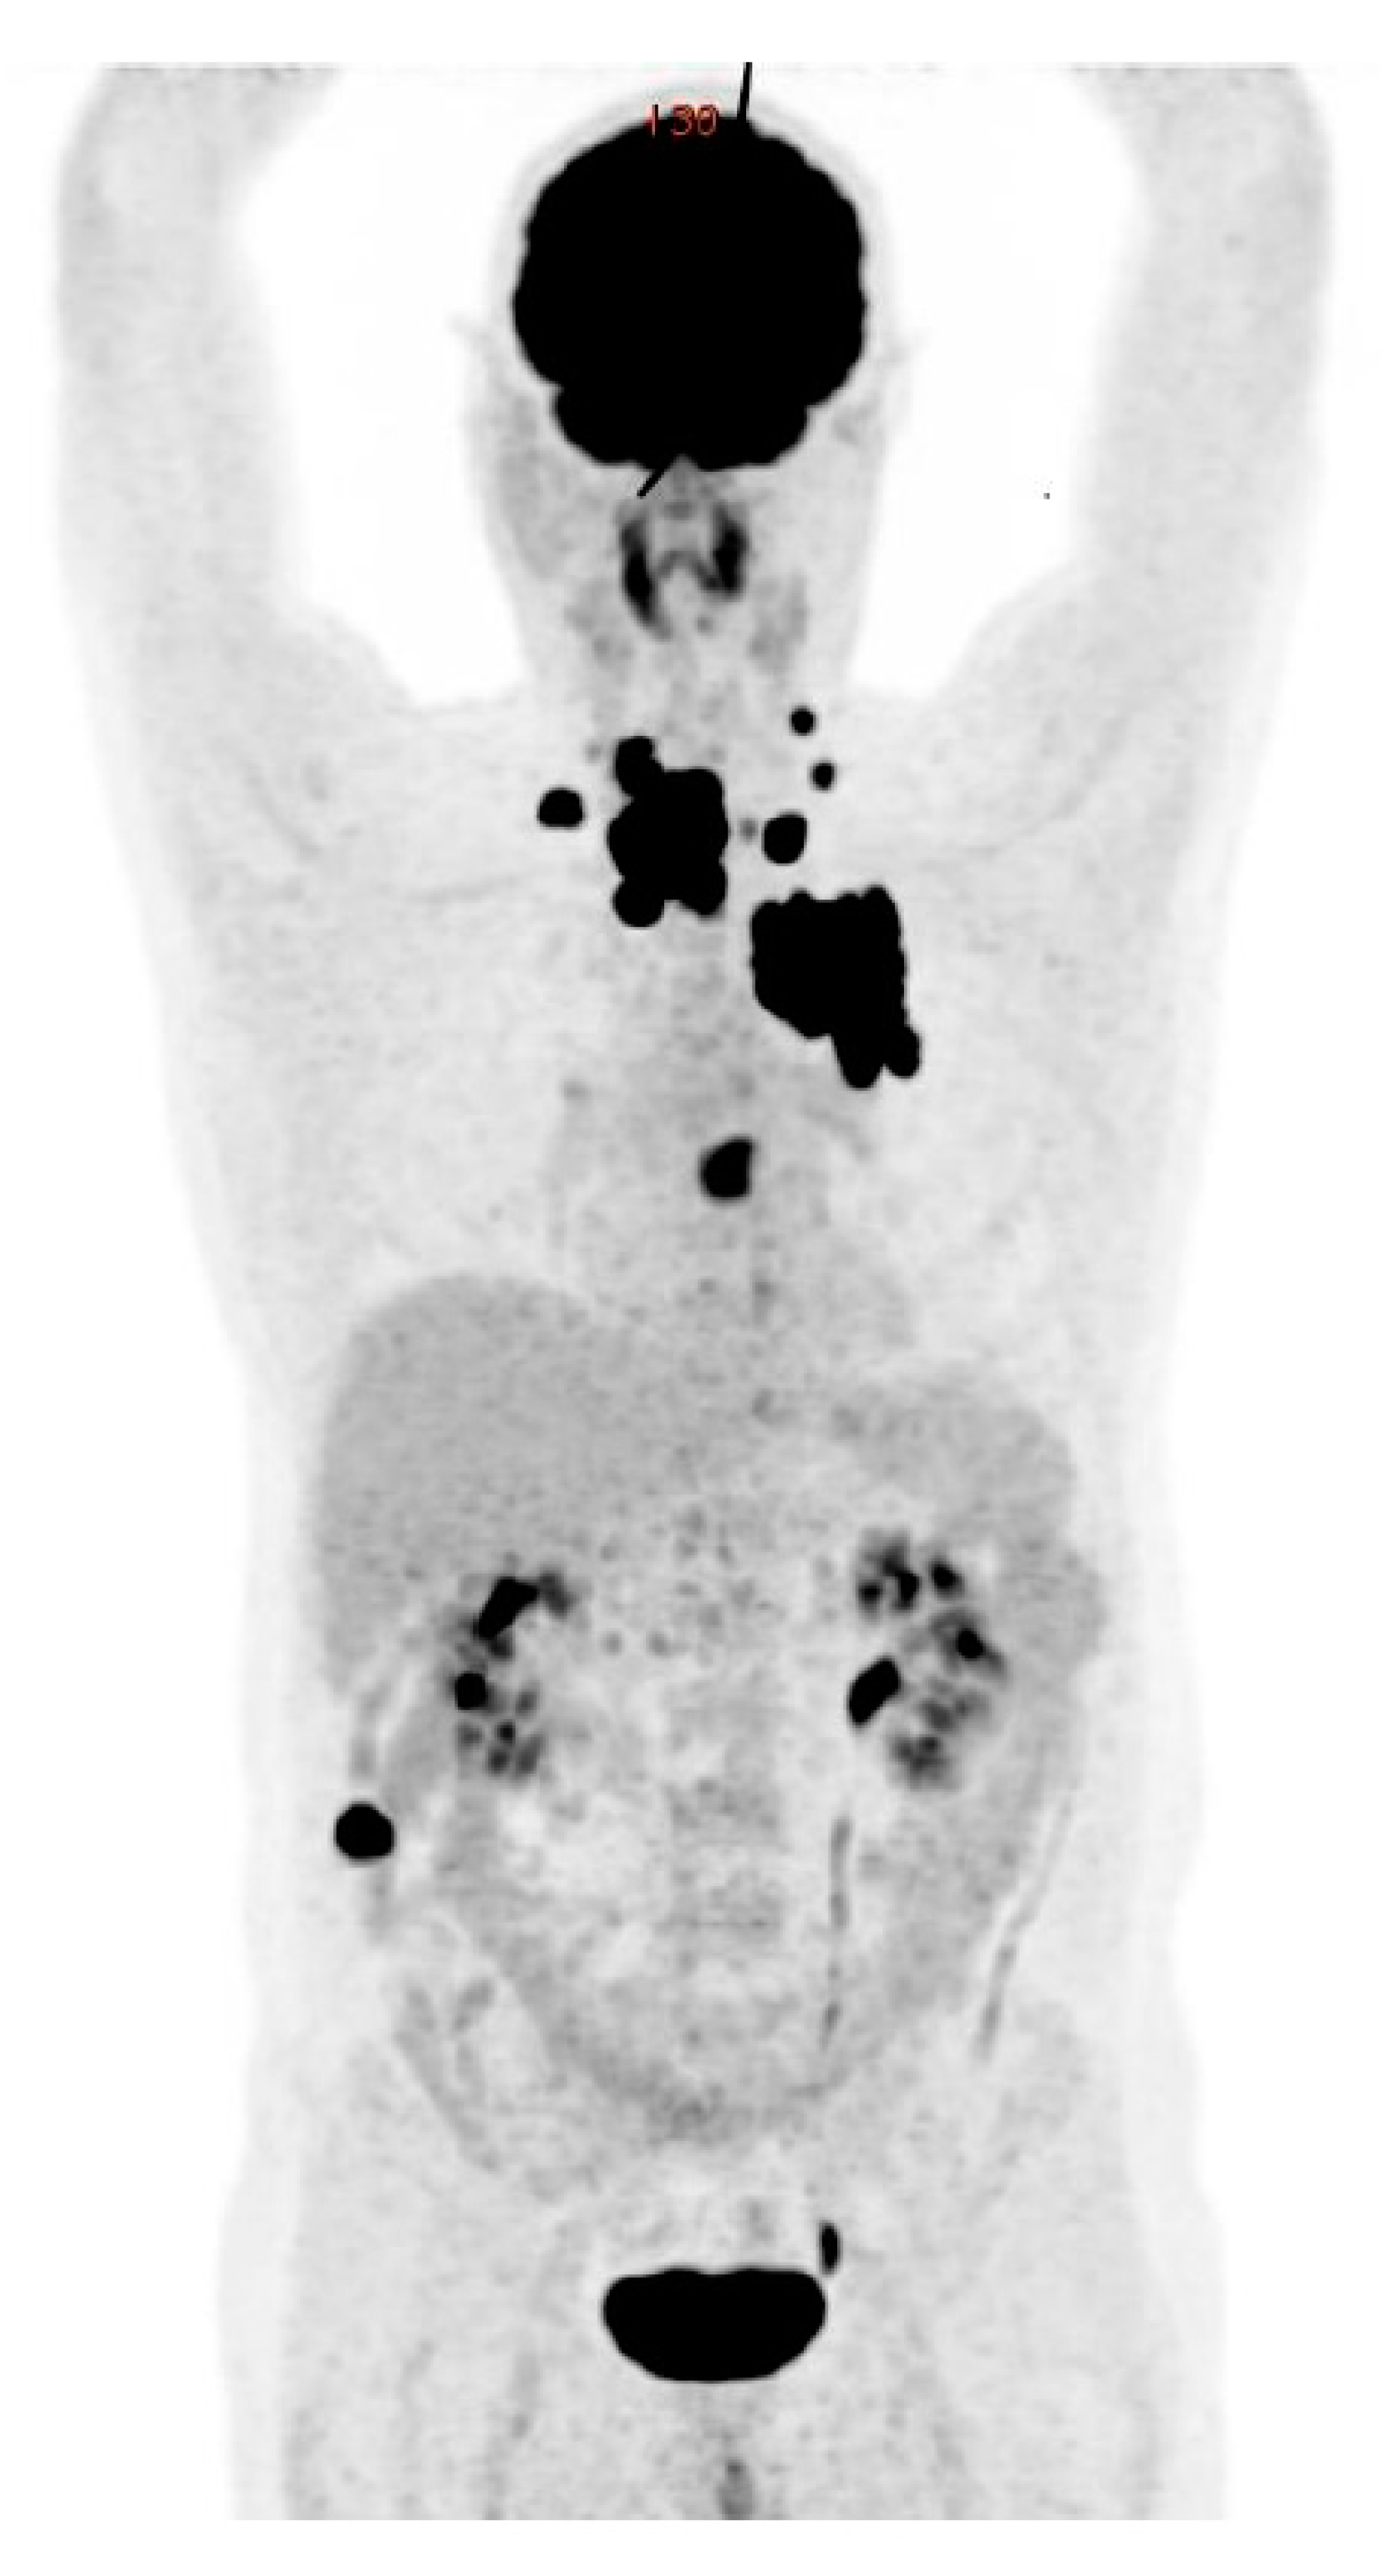

7.3. Molecular Imaging and Theragnostics